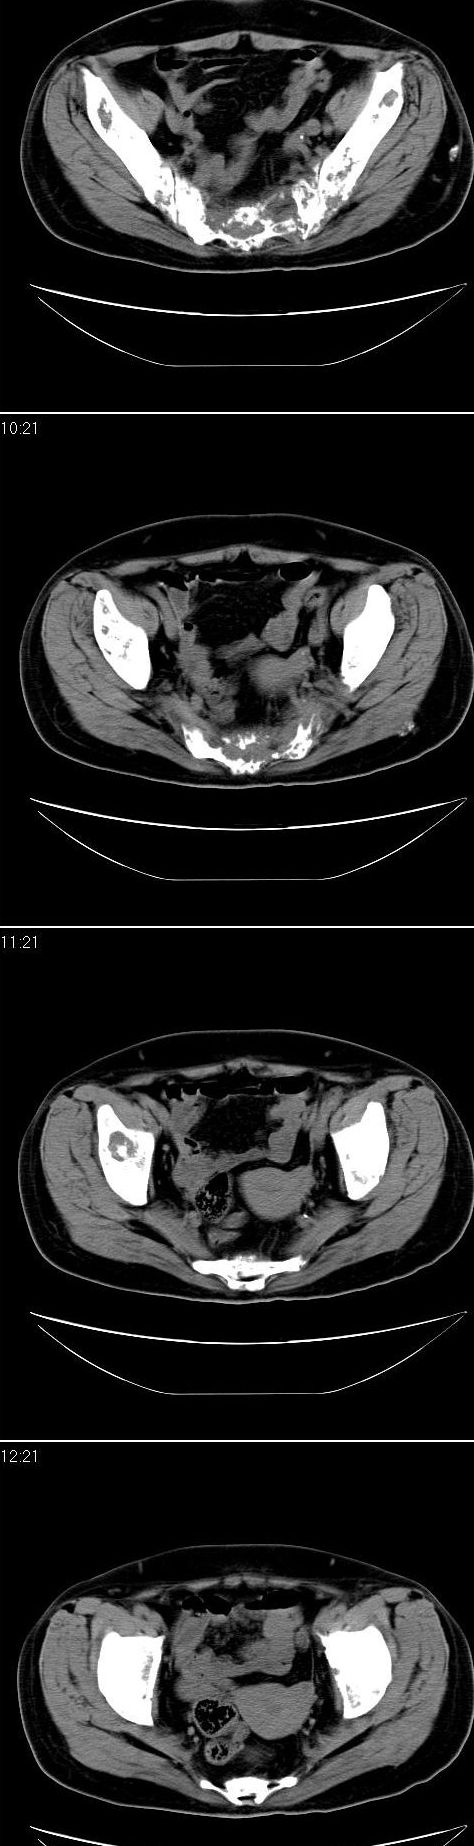

标题: CT13121:女,54岁。乳腺癌术后8年。 [打印本页]

女,54岁。乳腺癌术后8年。现感觉左腿酸困不适,并向下放散。左腿僵硬,不由自主。

典型溶骨型转移瘤。

骨盆及腰椎多发性溶骨性转移瘤.

成骨及融骨转移。

结合病史考虑乳腺癌术后多骨骨转移。

患者臀部皮下脂肪、筋膜、臀大肌处多个小结节、钙化影,看来挨了不少肌肉注射的苦头

支持 骨转移瘤---混合型以溶骨为主

结合临床考虑多骨多灶性溶、成骨性转移。